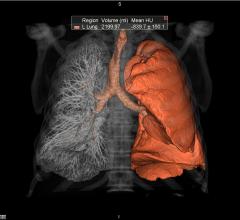

Contributing Editor Greg Freiherr offers an overview of computed tomography (CT) advances at the Radiological Society of North America (RSNA) 2015. The video includes Freiherr during his booth tours with some of the key vendors who were featuring new technology.

Technology Report:

Computed Tomography (CT)